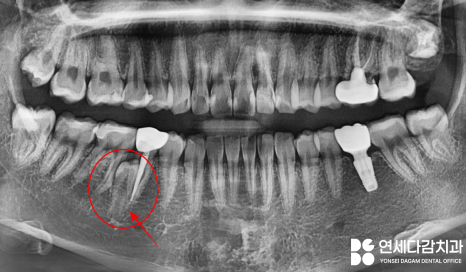

2023.12.18

연세다감치과 에서 수술 전

촬영한 CT사진입니다.

2차원 파노라마 뿐만 아니라

3차원 CT를 통해

매복된 정도와 위치를 정확하게 파악한 뒤,

주변 구조물이 손상되지 않도록

조심스럽게 뽑는 것이 중요합니다.

과잉치의 정확한 위치를 찾아낸 뒤

설측으로 잇몸을 절개하여 당일 발치를 마쳤습니다.